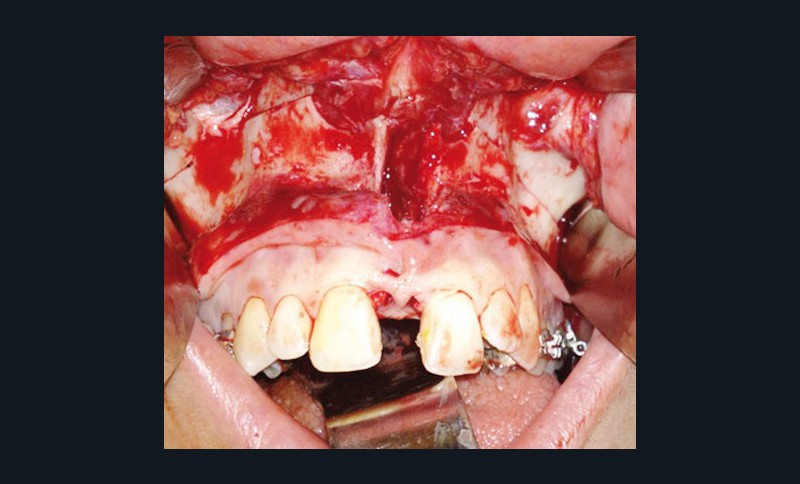

Étapes de traitement

(fig. 2, 3, 4, 5 et 6)

Le plan de traitement retenu a été le suivant :

– disjonction maxillaire assistée chirurgicalement

– préparation orthodontique avec recul molaire mandibulaire sur miniplaques à l’aide de corticotomies alvéolaires

– chirurgie d’avancée mandibulaire et génioplastie soustractive verticale

– finitions orthodontiques et éducation fonctionnelle active labio-linguale

– contentions collées maxillaire et mandibulaire

– suivi, en particulier de la fonction linguale